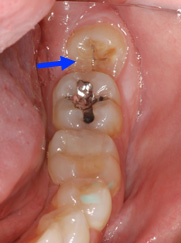

Lorsqu’une dent est partiellement sortie, la gencive la recouvrant constitue un endroit ou plaque et débris de nourriture peuvent s’accumuler et causer de l’infection, des caries et de l’inflammation. Il est alors indiqué soit de dégager la dent en enlevant l’excès de gencive ou de la faire extraire si la dent ne peut être dégagée convenablement pour compléter son éruption.

Une troisième molaire semi-incluse est plus difficile à nettoyer et peut carier plus facilement. Cette dent présente un début de carie dans les sillons de la surface.